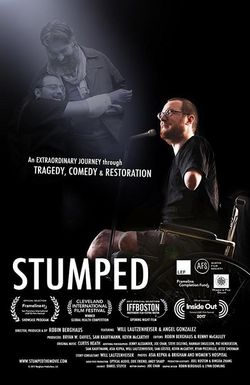

The film follows an artist's courageous and humorous response to a death sentence, as he battles ALS. Despite the degenerative condition, he adapts his painting techniques, switching from right to left hand, and then both hands held at his waist. With determination, he creates over 100 portraits in just four months.

Imber's Left Hand

An artist's courageous and uplifting story unfolds as he copes with an ALS diagnosis, transforming his challenges into opportunities for innovative expression.